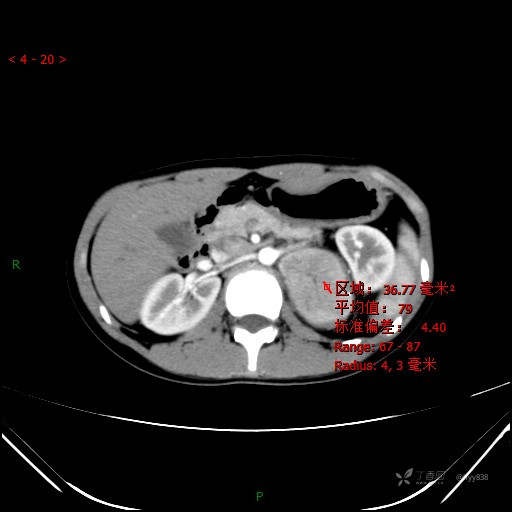

CT值